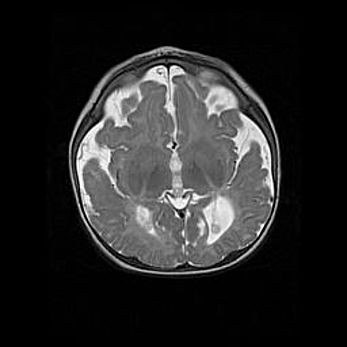

Лейкомаляция с кистозно-глиозной дегенерацией головного мозга.

Возраст: 2 месяца 25 дней

Вес: 6400 г

Окружность головы: 40 см

Срок гестации: 41 неделя

Лейкомаляцию относят к ишемически-гипоксическим повреждениям головного мозга, диагностируемым у новорожденных. При лейкомаляции в головном мозге обнаруживают очаги некроза, возникшие после тяжелой гипоксии и нарушения кровотока. В процессе морфогенеза очаги проходят три стадии: 1) развития некроза, 2) резорбции и 3) формирования глиозного рубца или кисты. Перивентрикулярная лейкомаляция (ПЛ) встречается примерно в 12% случаев среди новорожденных, обычно – у недоношенных детей, причем, частота ее зависит от массы, с которой младенец появился на свет. Наибольшее число малышей страдает лейкомаляцией, если масса при рождении 1500-2500 г.